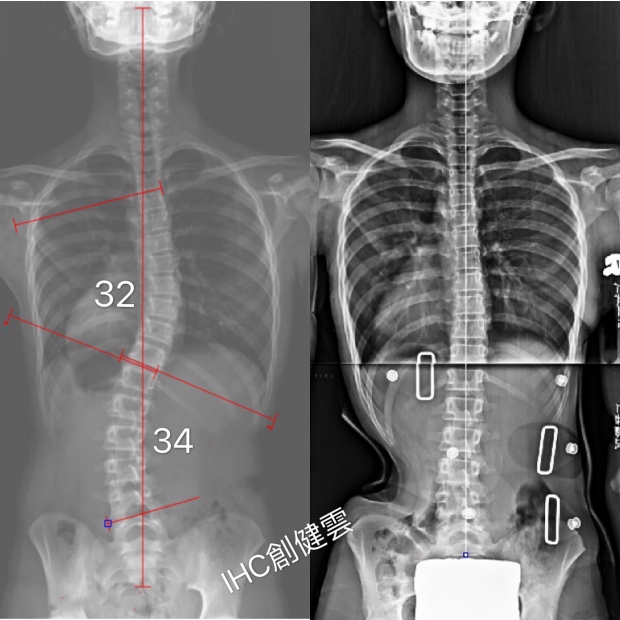

胸彎32度,腰彎34度

11歲S型脊椎側彎女孩